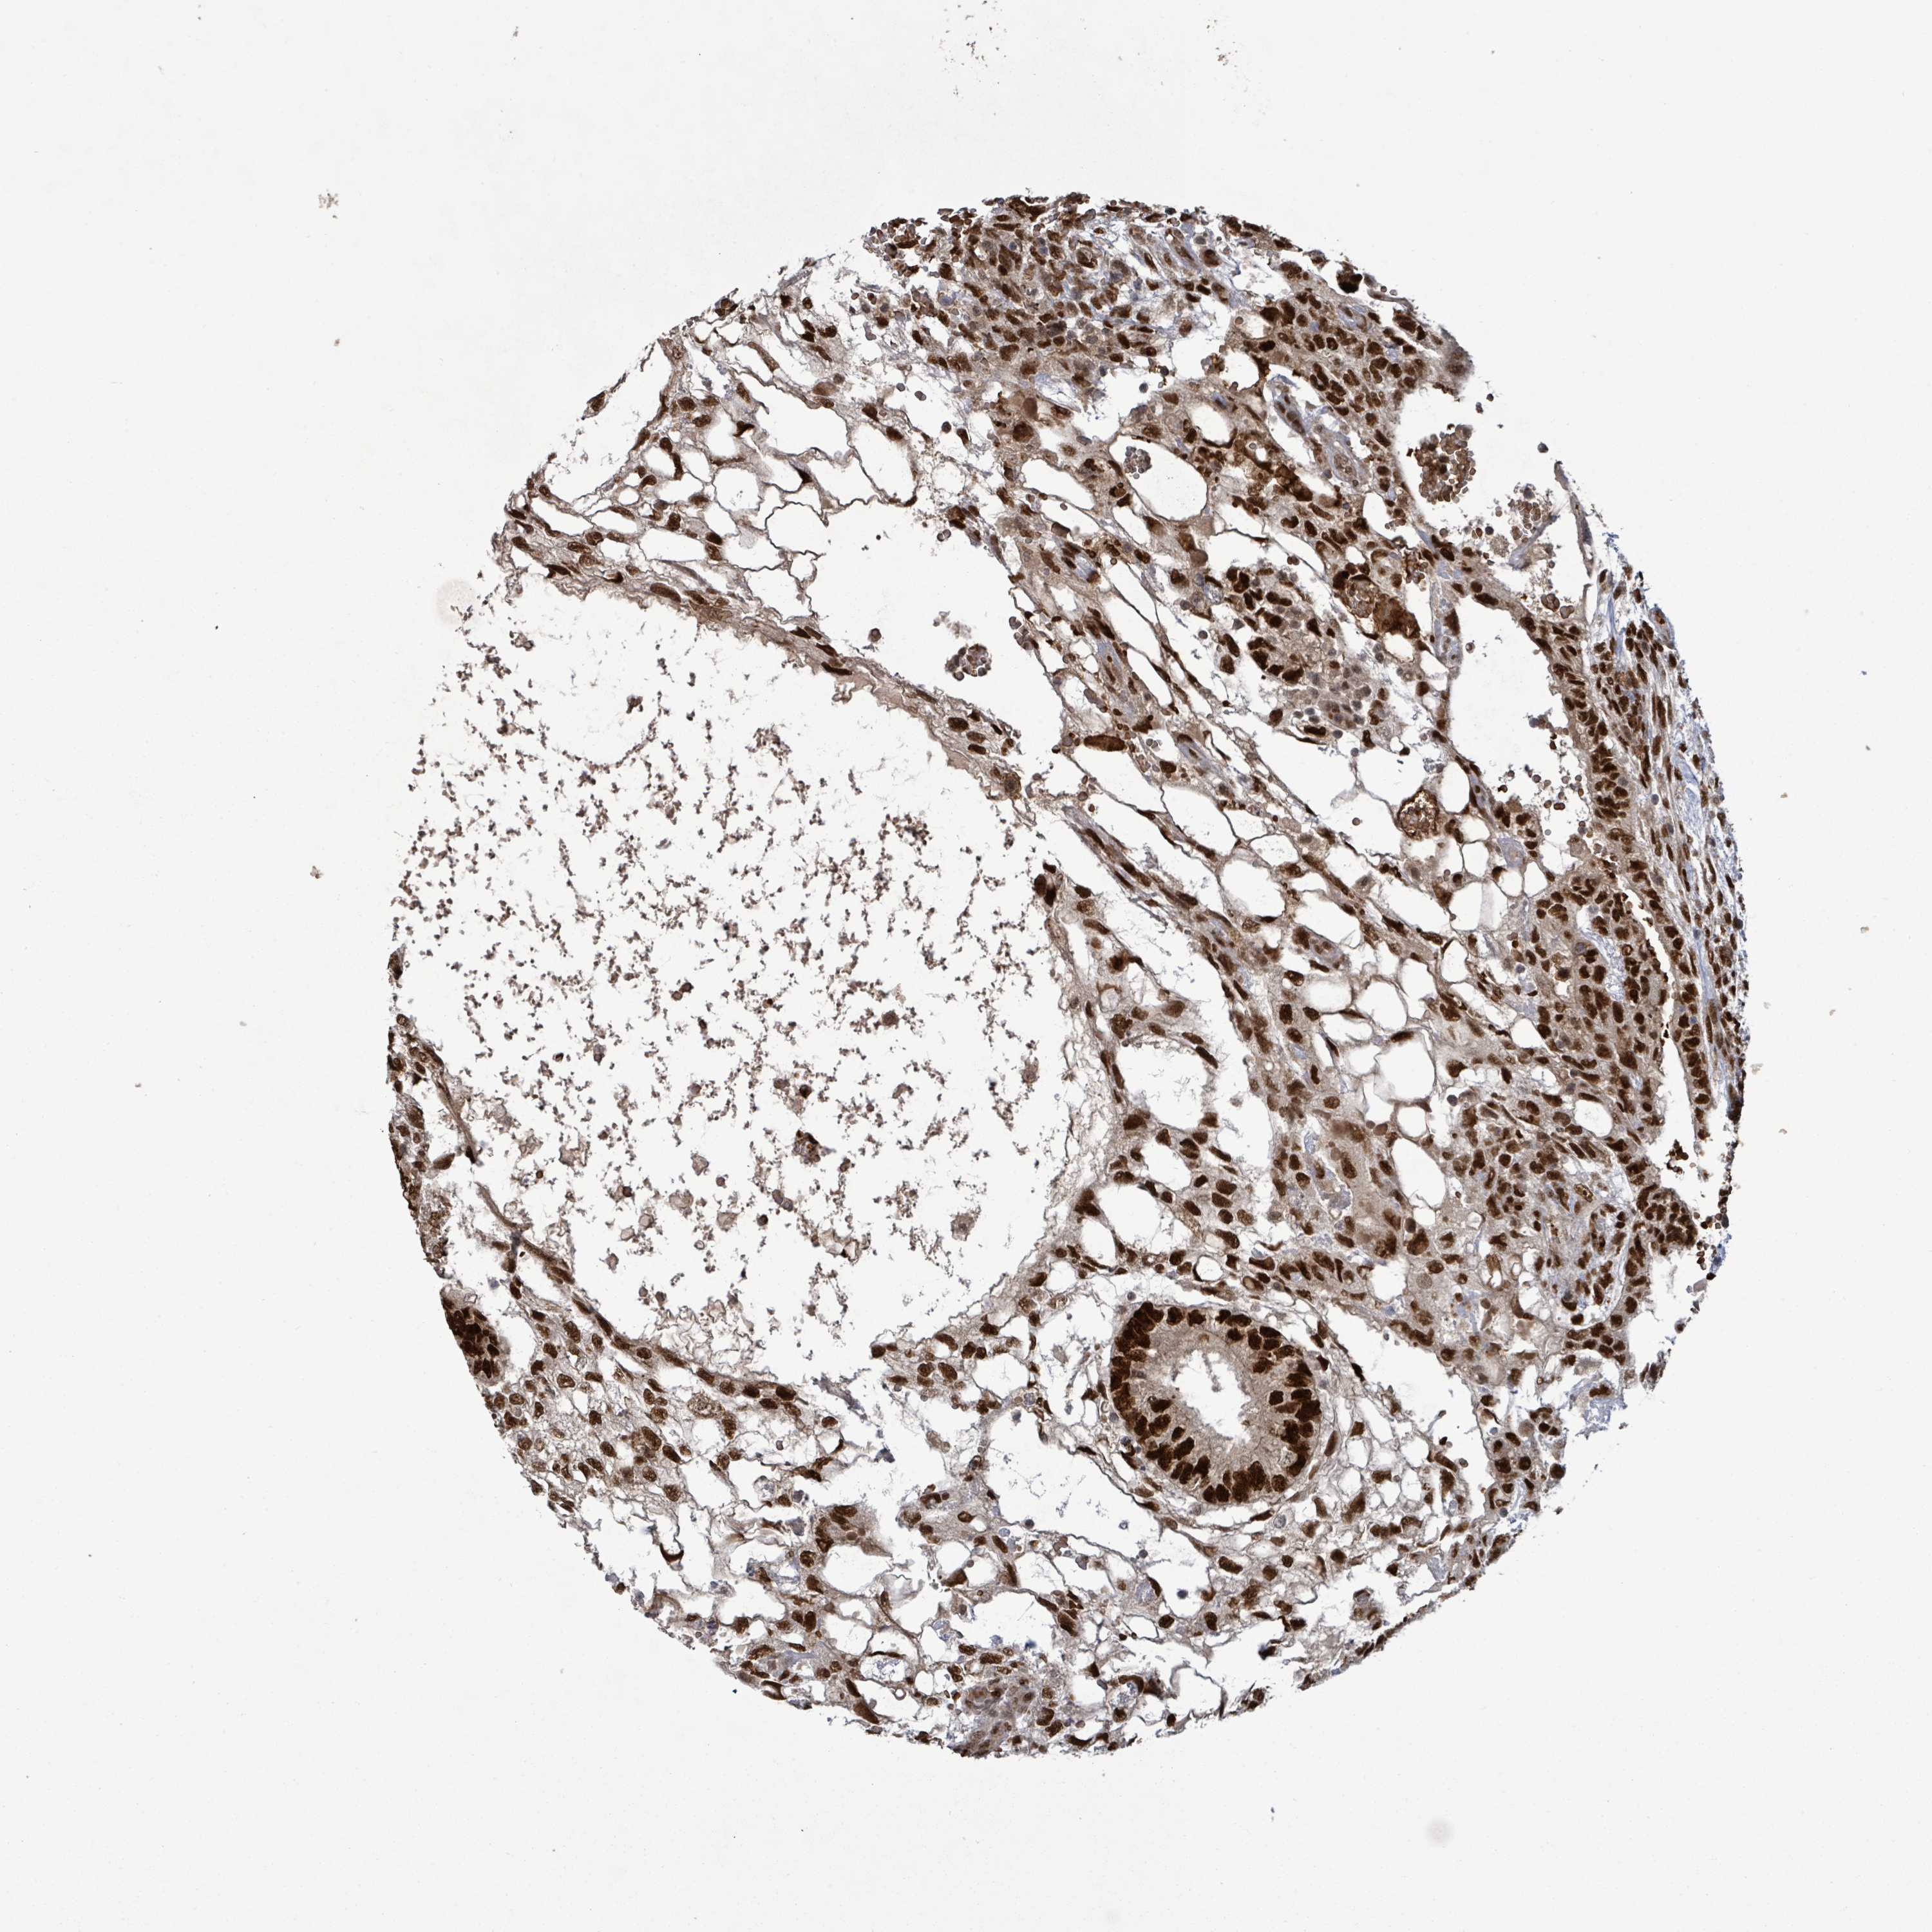

TESTIS CANCER - Protein expressioni

A mouse-over function shows sample information and annotation data. Click on an image to view it in a full screen mode. Samples can be filtered based on level of antibody staining by selecting one or several of the following categories: high, medium, low and not detected. The assay and annotation is described here.

Note that samples used for immunohistochemistry by the Human Protein Atlas do not correspond to samples in the TCGA dataset.

Antibody stainingi

Antibody staining in the annotated cell types in the current human tissue is reported as not detected, low, medium, or high, based on conventional immunohistochemistry profiling in selected tissues. This score is based on the combination of the staining intensity and fraction of stained cells.

Each image is clickable and will lead to virtual microscopy that enables deeper exploration of all samples and also displays staining intensity scores, fraction scores and subcellular localization as well as patient and tissue information for each sample.

Antibody HPA047893

Seminoma, NOS

Carcinoma, Embryonal, NOS